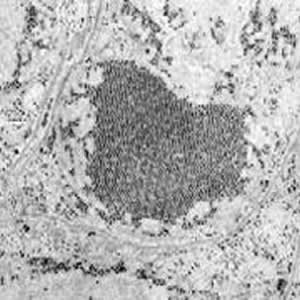

細菌が関節内や滑膜組織に侵入すると、滑膜組織に重度の炎症を引き起こします。また、感染に対する身体の反応により、関節液が劣化し、軟骨にダメージを与えます。

敗血症性関節炎は、感染後数日で関節に深刻なダメージを与え、重度の変形性関節症を引き起こします。